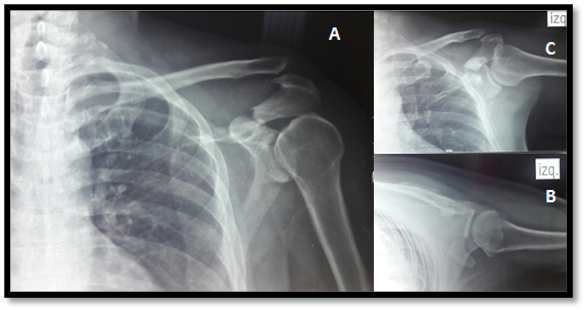

En las radiografías iniciales se evidencia una fractura desplazada del acromion, tipo II según la clasificación de Kuhn y una luxación acromioclavicular tipo III, según la clasificacón de rockwood (Fig 1).

Figura 1. Radiografías iniciales evidencian una fractura desplazada del acromion tipo II de Kuhn y una luxación acromioclavicular grado III de rockwood. Proyección anteroposterior de hombro (A), lateral (B), axilar (C).